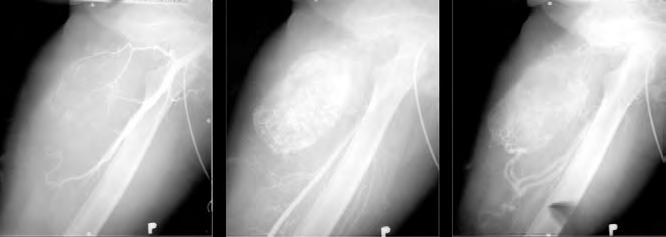

7.2.10 Hemofilický pseudotumor 139